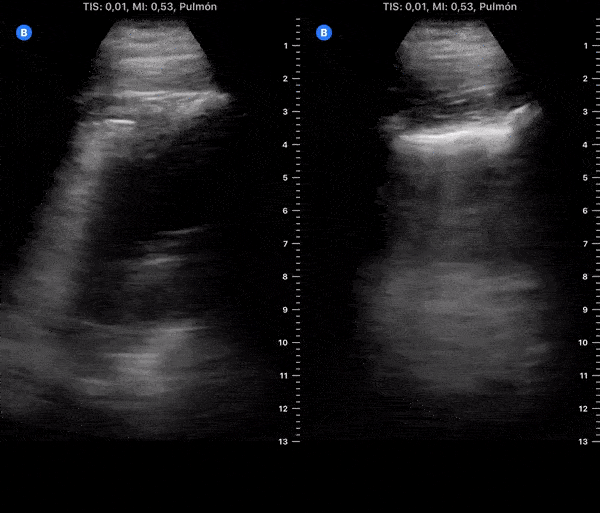

COVID 19 Lung US Disease Progression - Day 19

Day 19 after #COVID diagnosis. More cough & weakness. No fever or dyspnea. SpO2 97%. #POCUS update: Subpleural consolidation got bigger on left lower lobe. Yesterday started levofloxacin (bacterial super infection?). @yaletung